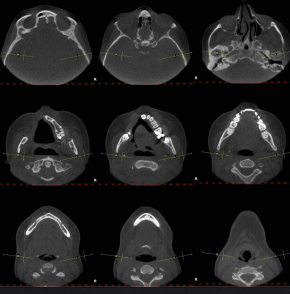

axial sections

coronal sections

saggital slicing

transaxial sections